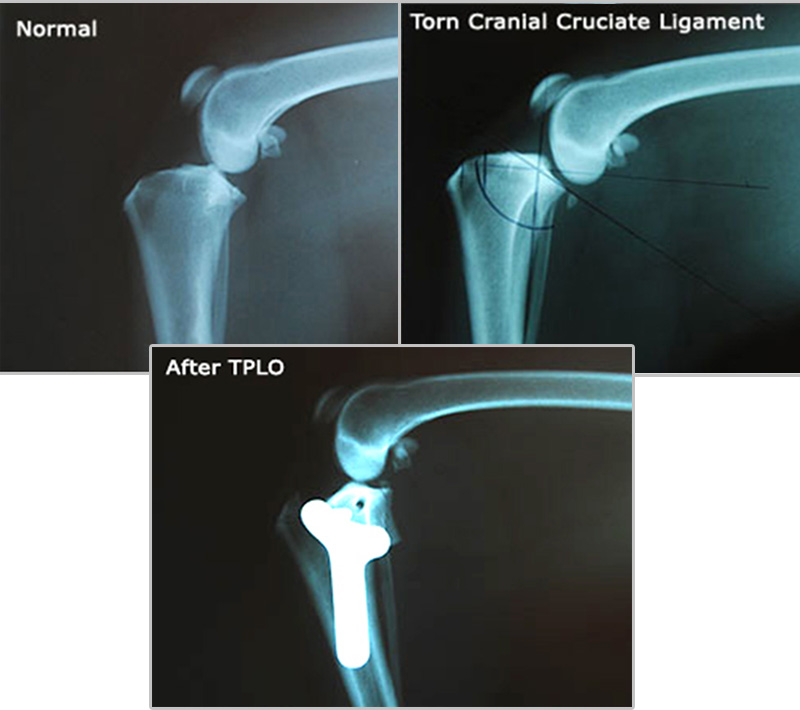

Radiographs (X-rays) Of A Dog's Knee With A Torn Cranial Cruciate Ligament

Following initial diagnosis and as part of the evaluation for TPLO surgery, the knees will be radiographed. In the x-rays below, the first X-ray shows a normal leg with the femur in proper position on top of the tibia. In the second x-ray, the ligament is torn, and the femur has slid backwards down the slope of the tibia. On the abnormal x-ray, the doctor has taken some measurements and marked the x-ray in preparation for the TPLO procedure.

- Postoperative Xrays are taken to assess the new tibial plateau angle and verify correct positioning of the plate and screws. In the X-rays below, the leg has been corrected by TPLO, and the femur is now resting securely on top of the tibia, in a similar position to the normal joint.